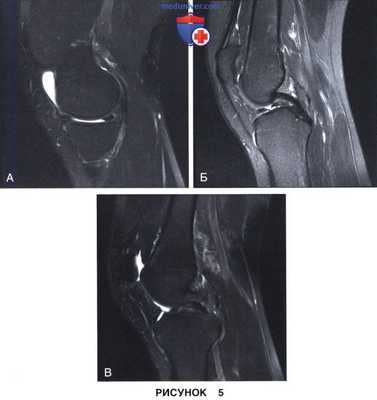

• Разрыв типа «ручки лейки» с дислокацией:

- На МР-томограммах при разрыве мениска типа «ручки лейки» в сагиттальной проекции отмечается дефицит заднего рога мениска (рис. 5, А) и симптом «удвоения задней крестообразной связки» за счет смещения поврежденной части мениска в межмыщелковую вырезку (рис. 5, Б). На другом сагиттальном срезе также виден смещенный в межмыщелковую вырезку фрагмент мениска (рис. 5, В)